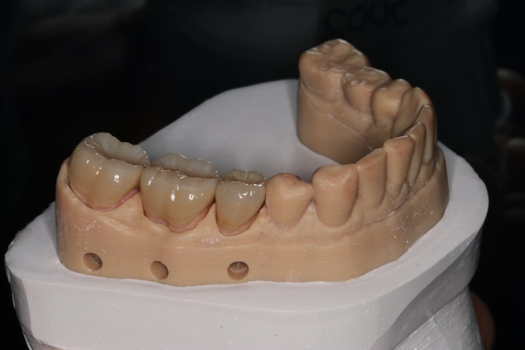

After completing an initial diagnostic appointment, a patient accepted three single-unit full-contour zirconia crowns that were milled from the digital impression and cut back for porcelain application. The application by a technician is analog dentistry. The ability of a dental laboratory to scan an analog crown-and-bridge impression is called converting an analog impression to a digital impression. The workflow after the conversion has become digitized. A dental model is virtually created with computer software, and a full crown proposal is fabricated for inspection virtually before the crown is milled (Figure 2). Due to the color of the digitized impression, the margins of the crown preparations are more easily and rapidly identified. The laboratory will also 3D print a working model, which will be used to develop the morphology of the final restoration by hand placement of porcelain (Figure 3). The decision to prescribe a full contour zirconia crown with cutback for porcelain application or complete full contour zirconia crowns lies solely on the attending dentist.9 A discussion with the patient before preparation of the teeth is imperative. After the discussion, the patient requested the zirconia copings with cutback and porcelain application for the posterior crowns (Figure 4 and Figure 5).

Fig 3. 3D-printed model.

Figure 3